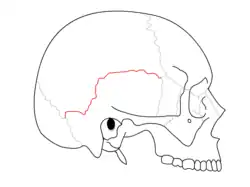

Suturas

Sutura escamosa separa osso parietal e o escamoso do osso temporal.

Sutura escamosa separa osso parietal e o escamoso do osso temporal. -

Vista lateral do crânio.

Vista lateral do crânio. -